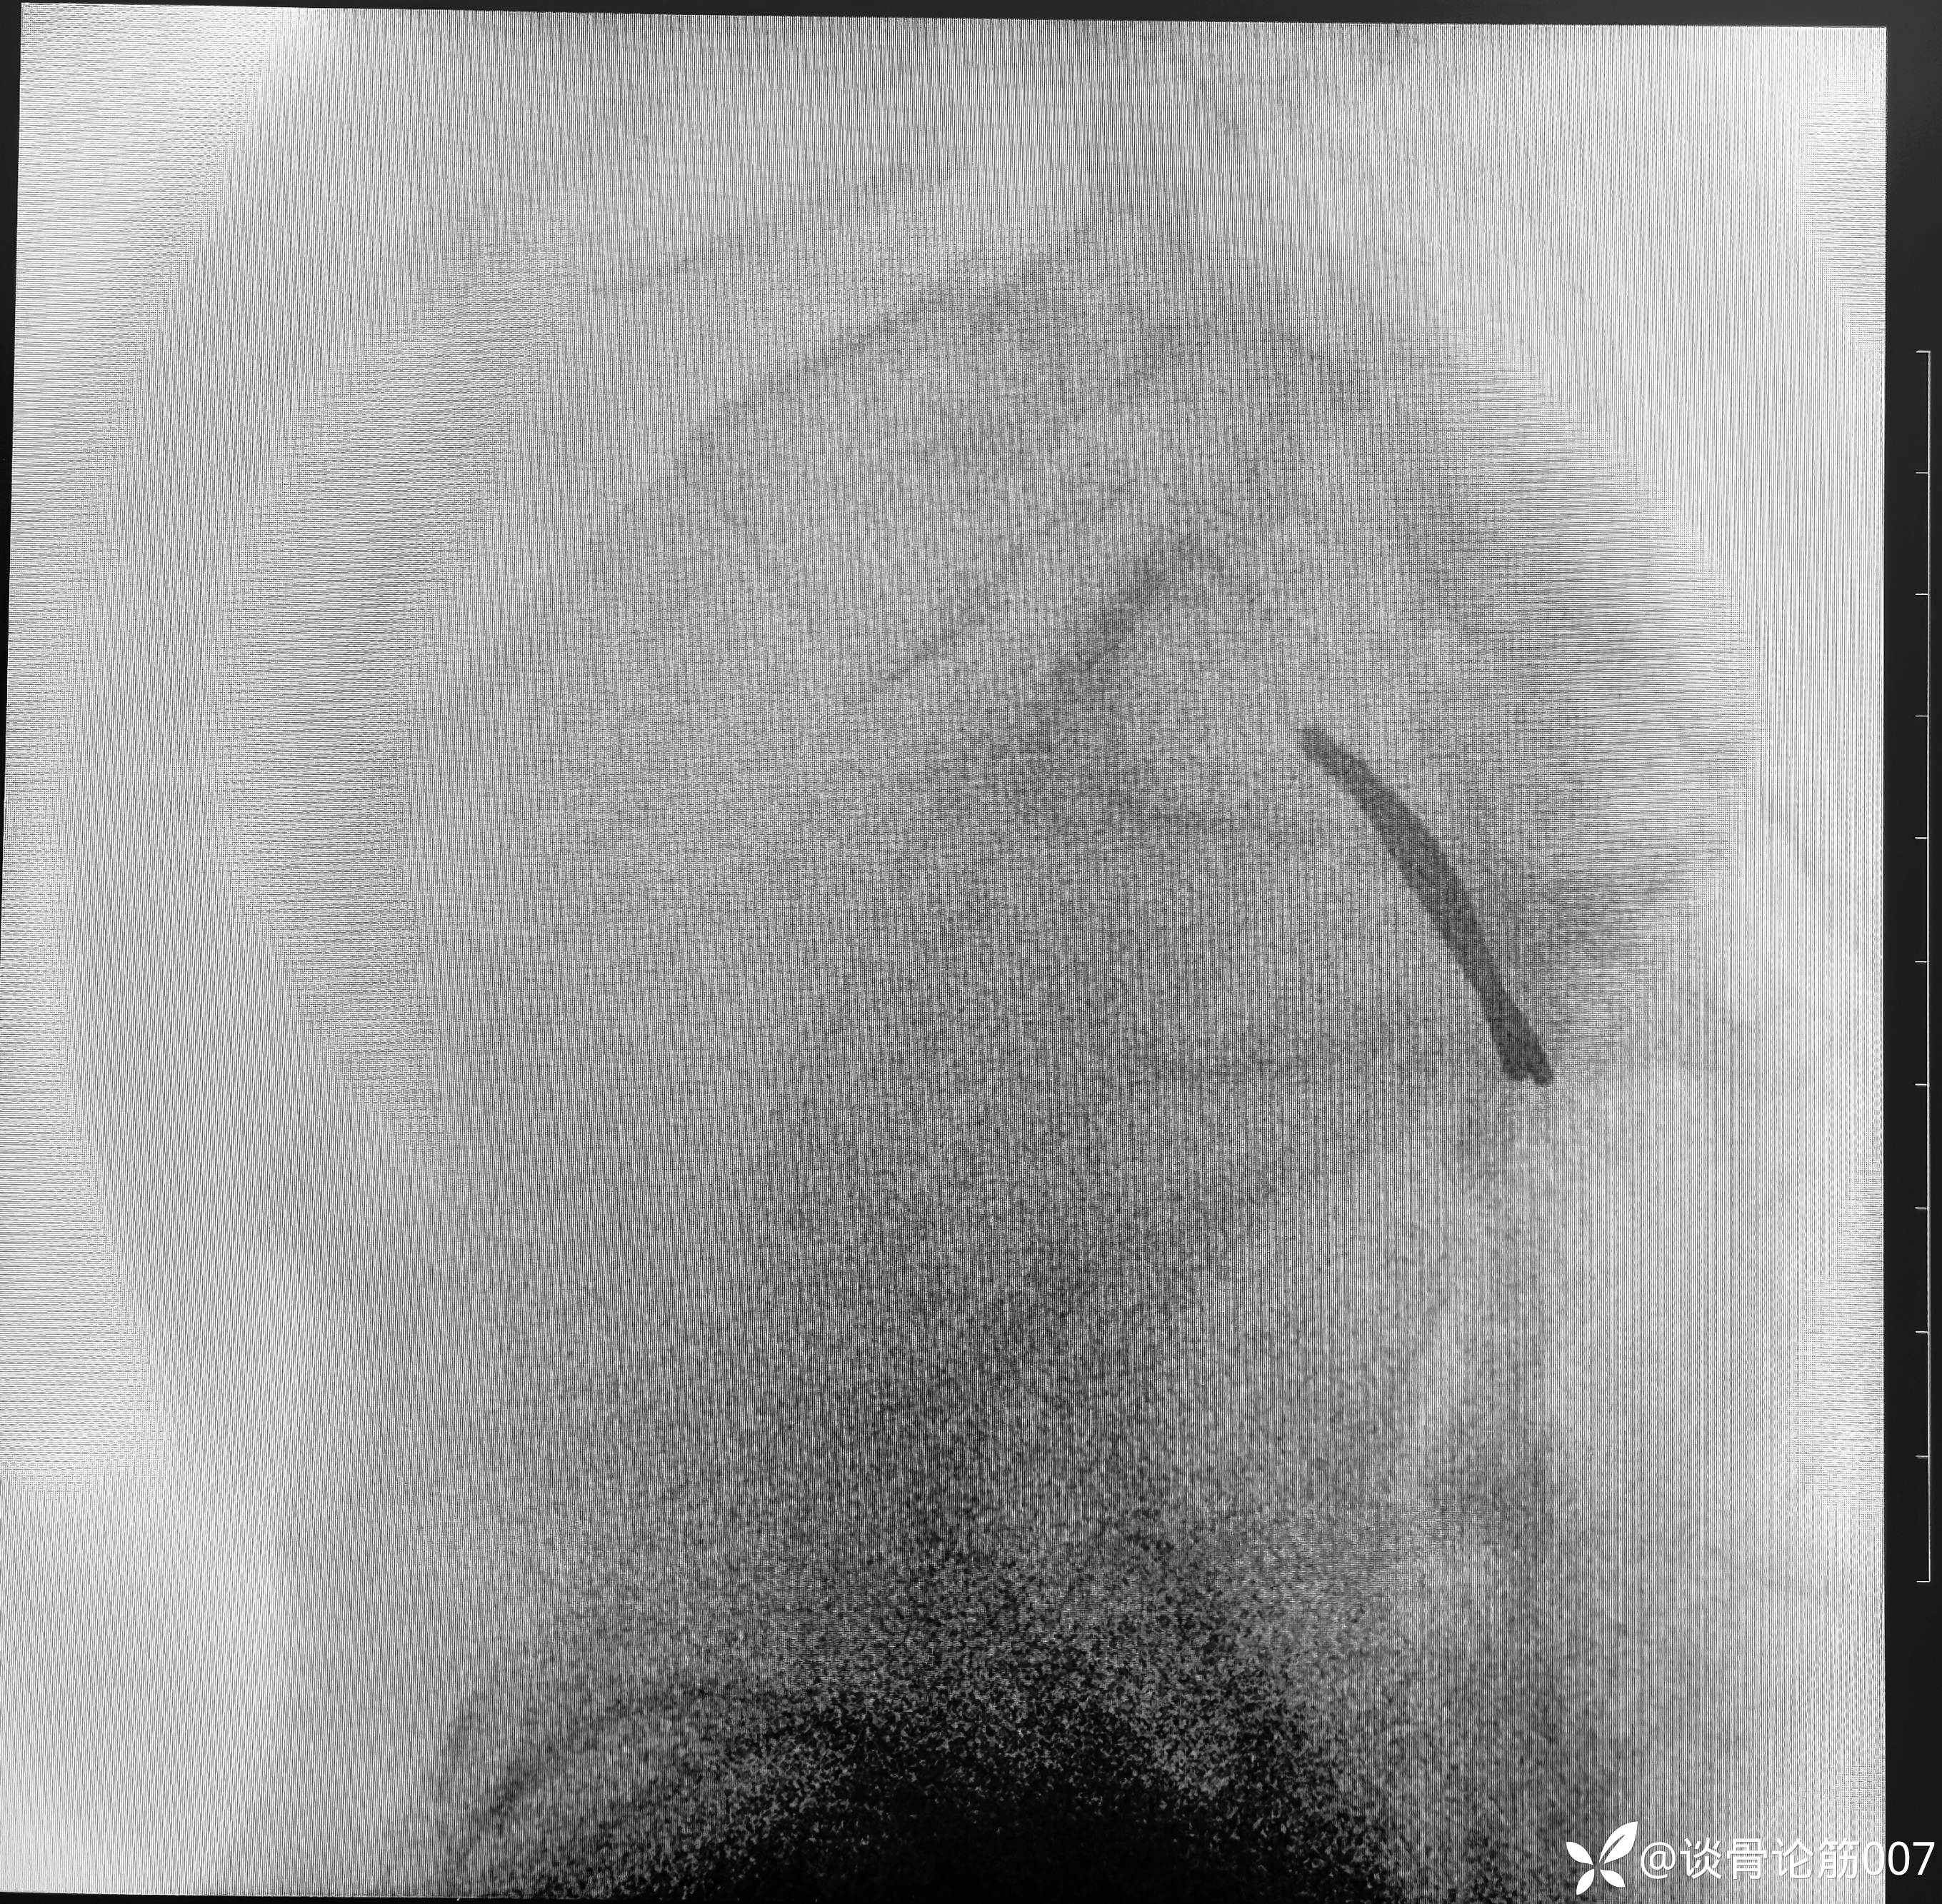

髂耻线比较高,骶髂螺钉相对简单一点

虽然术前进行导泄,通便,但腹部仍有积气,对透视还是有一定影响